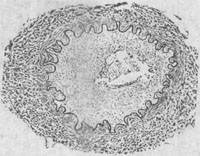

2.脑动脉炎 患者多为儿童,亦可为青壮年。患者常在急性期症状消失后1~5月出现偏瘫和失语等症状。主要病变是脑底多发性动脉炎及其所引起的脑实质损害。病变主要累及脑底动脉各干支,以大脑中动脉及大脑前动脉病变最重,大脑后动脉次之。病变呈跳跃性节段性分布,使该动脉粗细不匀、僵直或呈灰白色绳索状。此外,在基底节及其邻近脑实质内可见毛细血管及小静脉明显扩张充血,有的聚集成簇。镜下见受累动脉早期可为全动脉炎,较晚期则主要为增生性动脉内膜炎,使内膜显著增厚,可引起血管腔狭窄甚至闭塞,偶尔可并发血栓形成(图18-25)。脑实质可因缺血而发生轻重不一和不同部位的水肿、出血和多发性软化灶。

图18-25 钩端螺旋体病后发症——脑动脉炎模式图动脉内膜高度增生变厚,管腔变狭窄